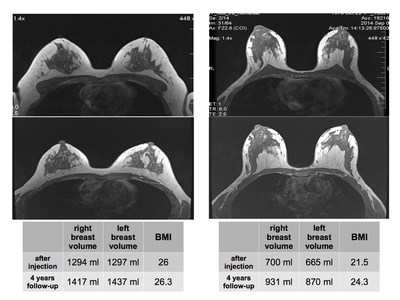

在医学主管Roberto Viel的医疗监督下,Bioscience Institute分别在ADSC治疗前和治疗4年后对乳房体积进行了MRI分析,分析结果显示,适量的脂肪注射可100%维持脂肪移植后达到的乳房体积。当患者身体质量指数(BMI)增加时,乳房总体积也会相应地增加,达到脂肪注射后实现的乳房总体积的109%至135%,这也证明了乳房的脂肪移植效果与其他身体器官的脂肪移植效果类似。